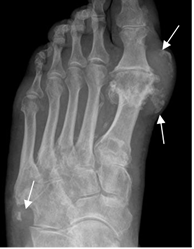

Fig 34. Artropatía por gota.

Rx AP del pie. Presencia de tofos calcificados, sobre el 1º y 5º dedo.